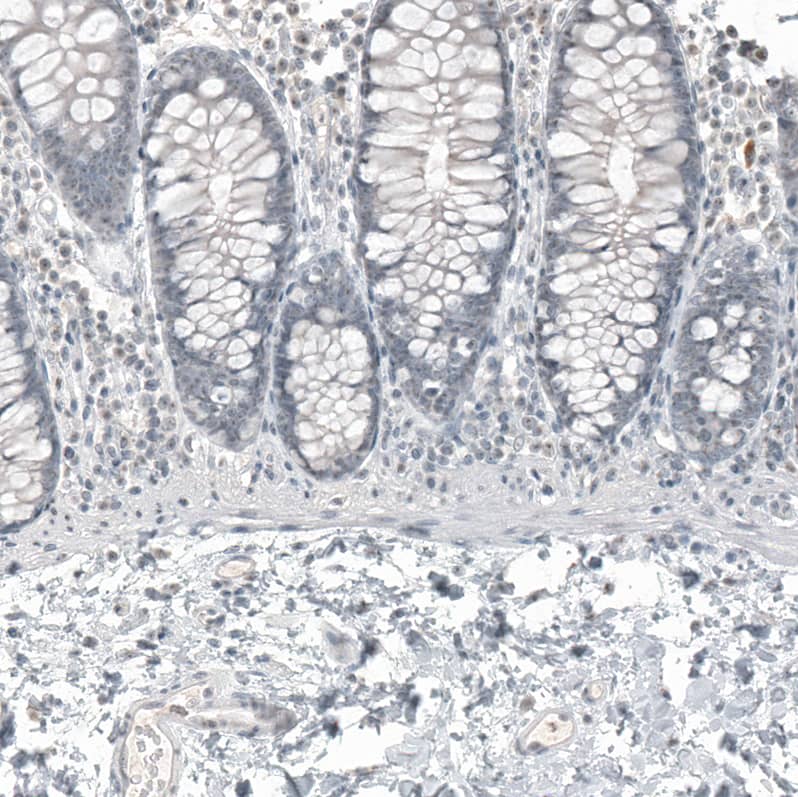

Staining of human colon shows no positivity in glandular cells as expected.